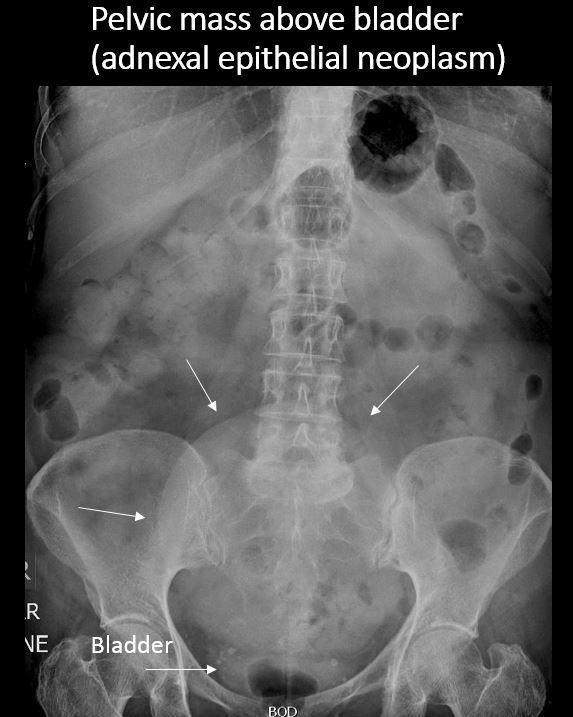

There is a soft tissue mass in the abdomen or pelvis. |

No | NA |

There are pelvic calcifications which could involve the uterus or adnexa. |

N/A | NA |